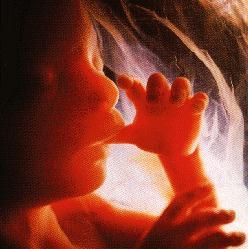

Развој бебе у стомаку мајке (фото) - улаз

Већина лекара који изводе чедоморства ради новца не дозвољавају мајкама да виде своје дете на ултразвуку нити да чују његове откуцаје срца да не би промениле одлуку.

78 % жена које виде ултра-звук бебе одбијају абортус! - погледајте

Снимак детета у стомаку мајке 3Д ултра-звуком: